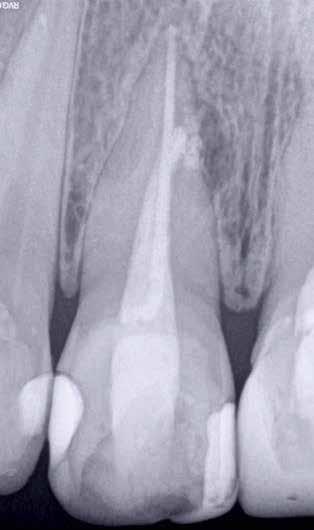

1. ábra: A 15-ös foggyökér meziális felszíne mellett látható radiolucens elváltozás, illetve a felvételen látható a korábban behelyezett gyökértömés, a parapulpális csap segítségével elhorgonyzott csonkfelépítés és a fogat borító cirkonkorona. –2. ábra: A saggitalis irányú CBCT-metszeten jól megfigyelhető az állcsontgerincet elérő radiolucens elváltozás. – 3. ábra: Az axiális irányú CBCT-metszeten egyértelműen látható a kezeletlen palatinális gyökércsatorna, valamint a radiolucens elváltozás mezio-disztális kiterjedése is jól megítélhető. – 4. ábra: A palatinális gyökércsatorna szelektív endodonciai kezelése során először gyógyszeres zárás került behelyezésre. – 5. ábra: A gyógyszeres zárás során alkalmazott kalcium-hidroxid alapú paszta a szulkuszon keresztül a szájüregbe extrudálódott. – 6. ábra: A gyökértömő anyag a középső és apikális gyökéri harmad határán lévő laterális csatornán keresztül a periapikális térbe extrudálódott. 7. ábra: A kezelések befejezését követően 4 évvel készült röntgenfelvételen jól látható a csontállomány gyógyulása és a fiziológiás gyökérhártyarés újbóli kialakulása. –8. ábra: A peroperatív CBCT-felvétel alapján készített koronális irányú metszeten jól látható a gyökércsúcs körül lévő periapikális felritkulás. – 9. ábra: A kezelések befejezése után 4 évvel készített CBCT-felvételen a gyulladásos lézió teljes megszűnése észlelhető.

A CBCT-készülékek endodonciai alkalmazásának talán az az egyik legnagyobb előnye, hogy így olyan anatómiai struktúrák is láthatóvá válnak, amelyeket egyébként nem tudnánk detektálni panoráma, cephalo, vagy periapicalis felvételek segítségével. Mivel a CBCT-felvételek kiértékelése számítógép segítségével történik, így a felvételek vizsgálata során lehetőségünk van az adott területet több nézőpontból és több síkban is megvizsgálni. 2015 októberében egy korábban a rendelőnkben kezelt 55 éves férfi páciens azzal a céllal kereste fel ismét a rendelőnket, hogy másodvéleményt kérjen egy jobb felső kvadránsban található fogával kapcsolatban. Egy másik rendelőben történő vizsgálat során a panaszos fog törését vélelmezték és a fog eltávolítását javasolták, illetve arról is beszámolt, hogy az elmúlt hét során ezen a területen egy puha duzzanat is kialakult. A klinikai vizsgálat során a jobb felső első és második kisőrlő között (14–15) egy fluktuáló duzzanatot észleltünk az áthajlásban. Az 15-ös fog mesialis oldalán 12 mm mély tasakot szondáztunk. A páciens által hozott periapicalis felvételen a 15-ös fog gyökércsúcsának mesialis részén egy nagy kiterjedésű radiolucens elváltozás volt észlelhető (1. ábra). A saggitális síkban vizsgált CBCT-felvételen (Carestream CS 9000, Carestream Dental) a lézió valódi kiterjedése is láthatóvá vált (2. ábra). A megelőző endodonciai kezelések során csupán a bukkális csatorna került detektálásra és gyökértöméssel való ellátásra. Az axiális irányú CBCT-szeleteken egyértelműen látható volt az ellátatlan palatinális gyökércsatorna (3. ábra)

Először kalcium-hidroxid alapú ideglenes gyógyszeres zárás került a palatinális csatornába (UltraCal XS, Ultradent Products; 4–5. ábra), amelyet 6 hét után a végleges gyökértömés elkészítése előtt eltávolítottunk. A gyökértömés elkészítése során meleg vertikális kondenzációs technikát alkalmaztunk. Radiológiai felvételen megfigyelhető volt, hogy a gyökértömő anyag egy laterális csatornán keresztül kis mennyiségben a periapicalis térbe extrudálódott (6. ábra). A 4 évvel később készített kontrollfelvételeken a lézió gyógyulása volt megfigyelhető (7–9. ábra). A vizsgálati eredmények és a kezelés kimenetele egyértelműen igazolta, hogy nem gyökérfraktúrával álltunk szemben, tehát a kezdeti diagnózis tévesnek bizonyult. Ez is azt erősíti, hogy korlátozott mennyiségben rendelkezésre álló adatok alapján nem lehet pontos diagnózist felállítani. Manapság szinte elengedhetetlen a CBCT-felvételek endodonciai beavatkozások során történő használata, feltéve, ha ezek elkészítése során az ALARA elv (as low as reasonably achievable) betartásra kerül.